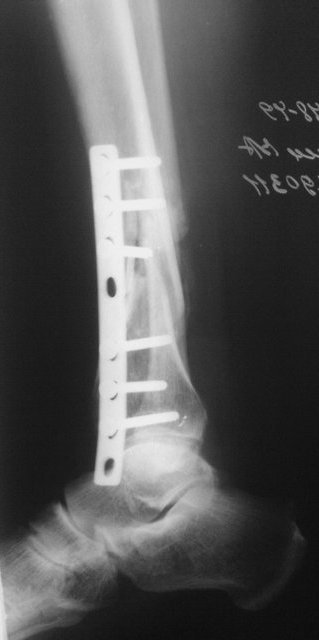

Примерная ситуация. Пациент 37 лет. Синтезировали где-то пластинкой. Попал к

нам через 2 месяца.

19 апреля  убрали через проколы пластину с винтами, пересекли fibula,

наложили аппарат.

Имя     : preop_1_ap.jpg

Тип     : image/jpeg

Размер  : 52784 байтов

Описание: отсутствует

Url     : http://weborto.net:8080/pipermail/ortho/attachments/20110817/7ada23a0/attachment-0006.jpg